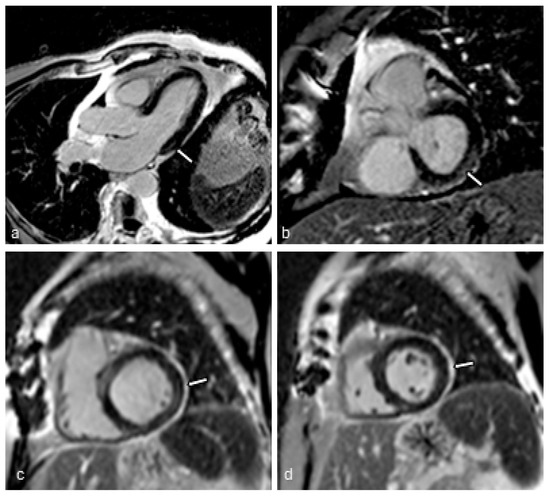

2.4. Cardiac MRI Protocol

2.4.1. Image Acquisition

2.4.2. Image Analysis

3.2. MRI Findings